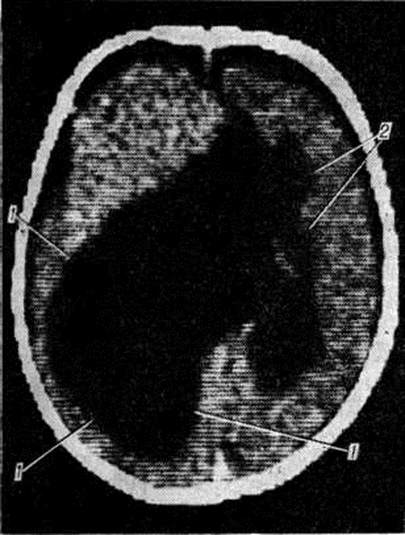

Форму и локализацию кист, особенно множественных, наиболее точно устанавливают посредством компьютерной томографии (смотри полный свод знаний: Томография компьютерная). При истинной Порэнцефалия на томограммах обнаруживают в головном мозге очаги пониженной плотности, соответствующей плотности цереброспинальной жидкости, с чёткими контурами, без явлений отёка окружающей ткани. При сообщении кистозной полости с желудочком мозга смещения его в противоположную сторону не отмечается (рисунок 4). При ложной Порэнцефалия в головном мозге выявляют очерченные кистозные полости; в случае их локализации в одном полушарии желудочки мозга нередко смещены в противоположную сторону.